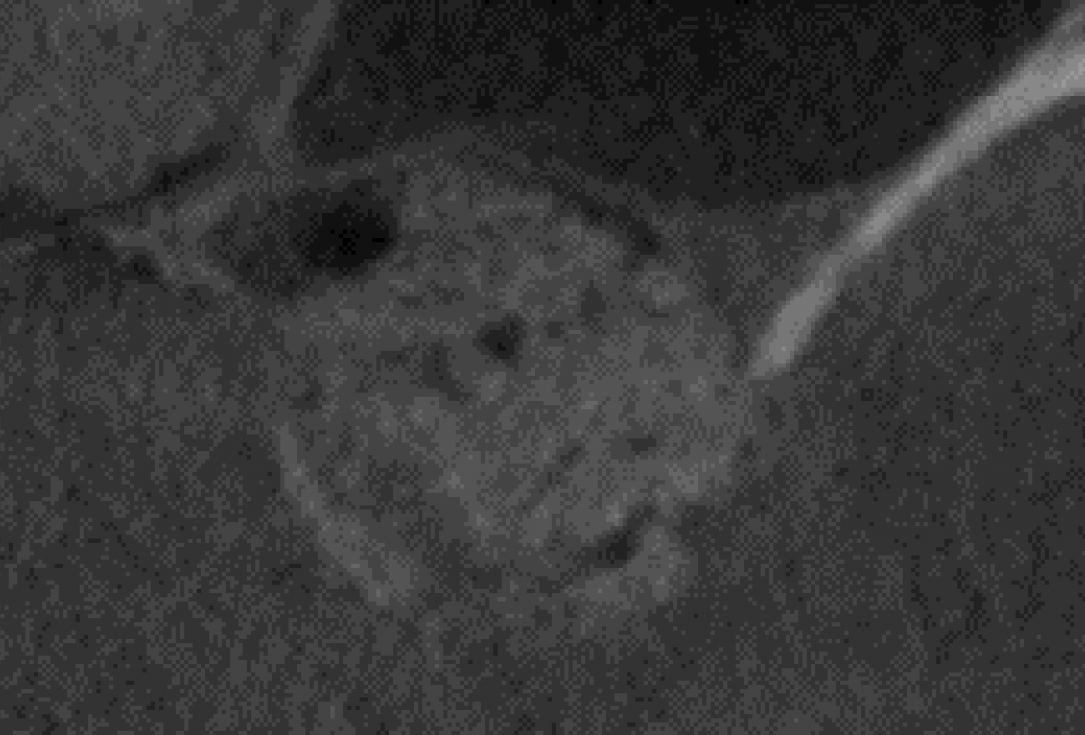

14/14 - x-ray control after uncovering showing dense regeneration of the graft material

Two-stage sinus lift with maxresorb® & collprotect® - Dr. S. Kistler